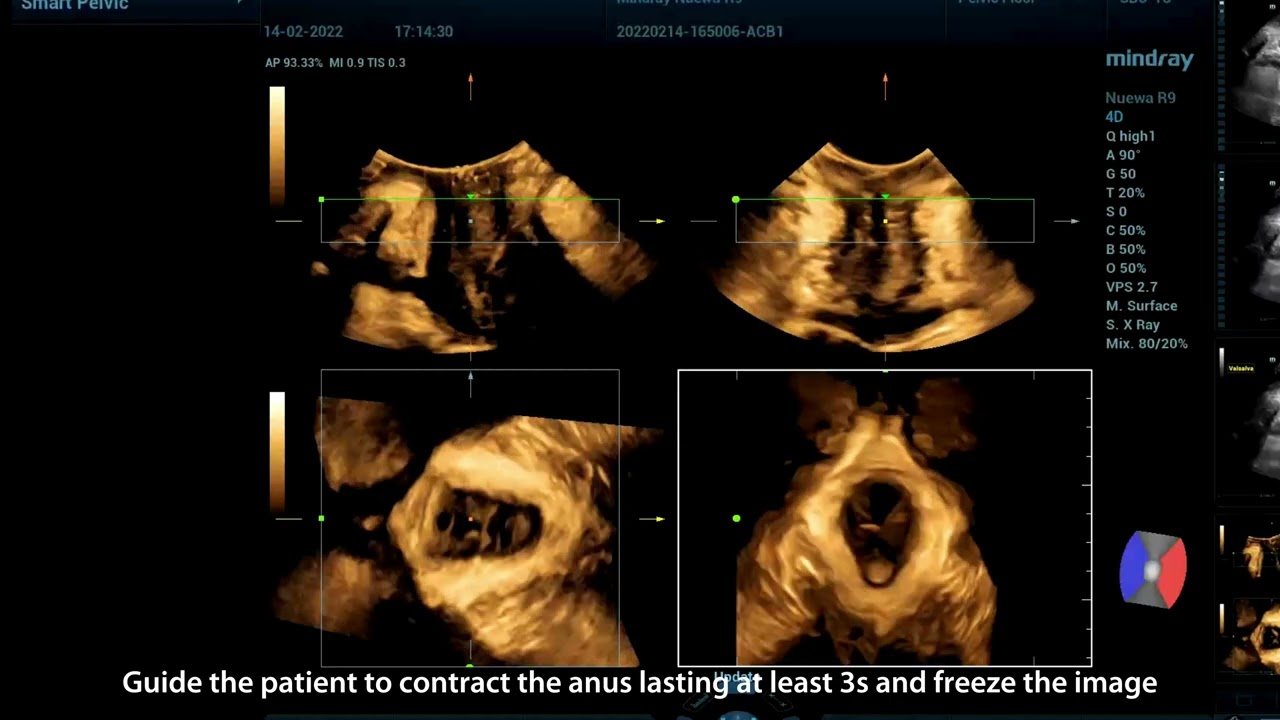

In the ultrasound diagnosis of FPFD, doctors promote a global approach to a comprehensive and accurate diagnosis of the anterior, middle and posterior pelvic compartments, in which it includes a large number of 2D measurement requirements, 3D/4D imaging and evaluation requirements, etc. The exam process is time-consuming and inconvenient, with high demands on imaging modes and fast measurements.

Nuewa provides automatic 2D measurements for the pelvic compartment and an intelligent volume evaluation system, including automated evaluation for levator hiatus and multi-section analysis with automatic measurements.